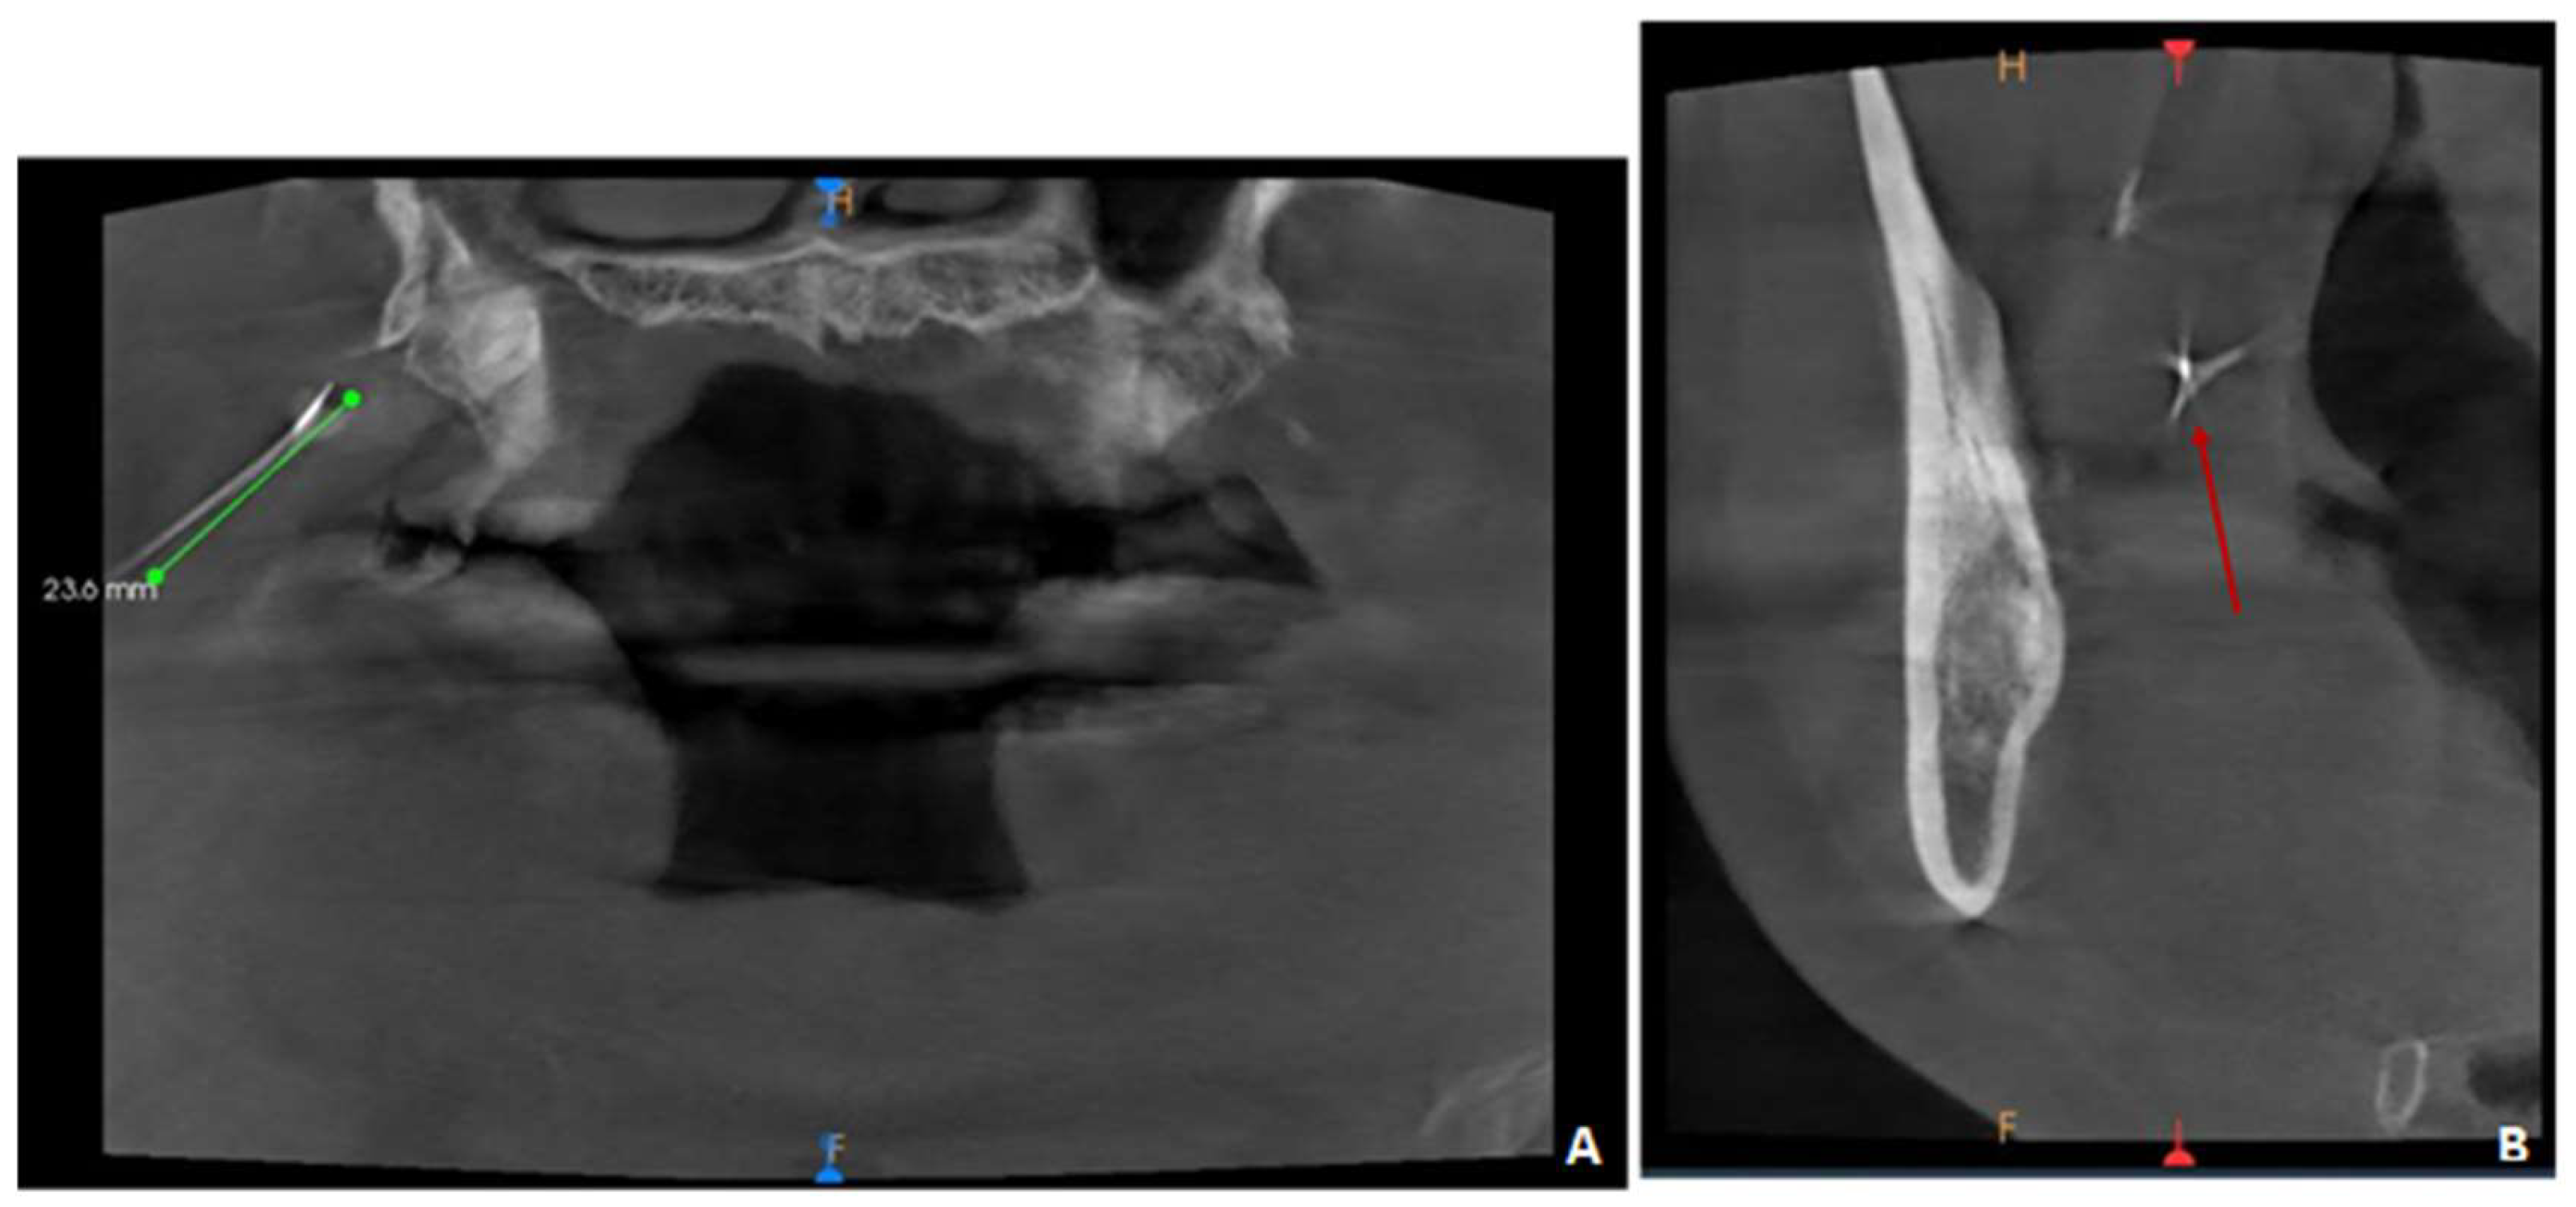

Preoperative radiographic images showing the broken needle in (A Needle Breakage In Dentistry Needle fracture during the delivery of local anaesthesia is a rare complication in modern clinical dentistry and to some extent has become a historical issue. But although rare, dental needle breakage can, and does, occur. The retrieval of a broken dental needle demands a detailed knowledge of the relevant anatomy and the application of a meticulous surgical technique. A broken. Needle Breakage In Dentistry.

Preoperative radiographic images showing the broken needle and Needle Breakage In Dentistry We report a case of. But although rare, dental needle breakage can, and does, occur. The retrieval of a broken dental needle demands a detailed knowledge of the relevant anatomy and the application of a meticulous surgical technique. Should a needle break, the practitioner must note how it. These factors are emphasized in the following article. Review of the literature. Needle Breakage In Dentistry.